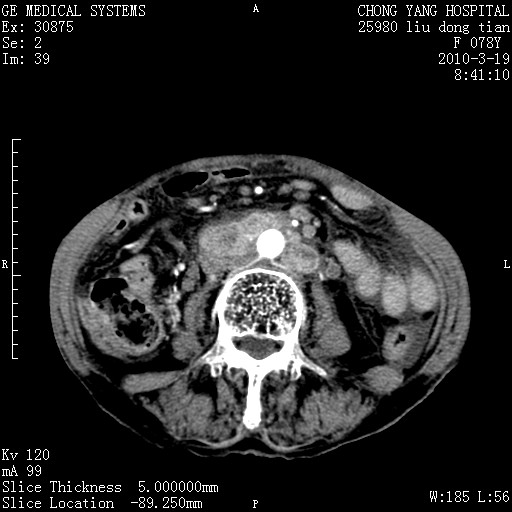

标题: CT25199:F 78Y 腹胀半年 消瘦乏力 [打印本页]

胆囊壁增厚并明显强化,胆囊癌伴多发转移瘤可能性大,淋巴瘤不除外,右肾囊肿,胸腹水.

考虑nhl,肝、脾、腹膜腔及腹膜后多发淋巴结受侵,腹水,右肾囊肿,慢性胆囊炎,右侧少量胸腔积液。

胰头有肿块形成,胰头ca伴肝脾、腹膜腹膜后转移

胆囊有软组织影有强化,支持胆囊癌,肝脾、腹膜后淋巴结转移。

nhl的淋巴结多围绕主动脉,而且主动脉会移位,所以不考虑nhl。

分开来讲:肝左叶、尾叶病灶有不均强化像肝癌;

脾脏病灶无强化,像多发囊肿或淋巴管瘤,不除外淋巴瘤(低强化);

胆囊增生性病变:胆囊癌,腺肌增生症,慢性胆囊炎;

肝门、胰腺头、腹膜后多个团块: 淋巴瘤,转移;

腔静脉肝内段细小有无布加可能?

一元论最好了 淋巴瘤所致改变; 胆囊癌转移不像,胆囊周围肝组织清晰,肝癌淋巴结转移?三元论都不止。

胰头ca伴肝脾、腹膜腹膜后转移!

最后报的胰头癌多发转移,脾脏单独考虑囊肿或淋巴管瘤。